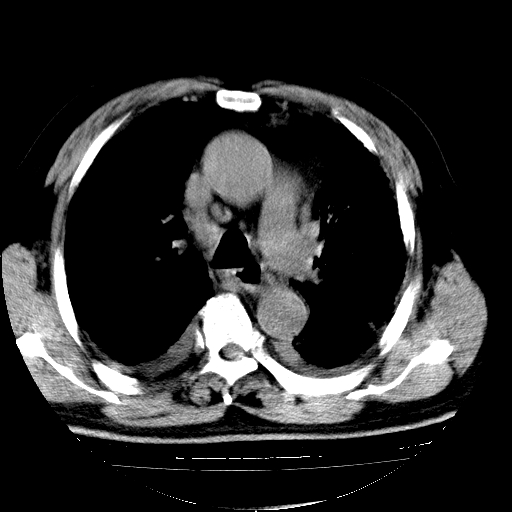

男,68岁,咳嗽、胸闷、发烧三天,查体:双肺散在湿罗音。

首先考虑特发型肺间质纤维化;两侧少量胸腔积液。

依据:1、两肺广泛条索状、网格状、蜂窝状改变。

1.双肺间质纤维化并感染;

2.双肺慢支炎肺气肿;

3.支扩并感染;

4.肺原性心脏病;

5.双侧胸腔少量积液;双侧胸膜增厚。

双肺多发条索状、网格状及小灶状密度增高影。考虑慢支合并感染.间质纤维化,双侧少量胸腔积液

两肺广泛条索状、网格状、蜂窝状改变。肺间质纤维化,肺心病,双侧胸腔积液